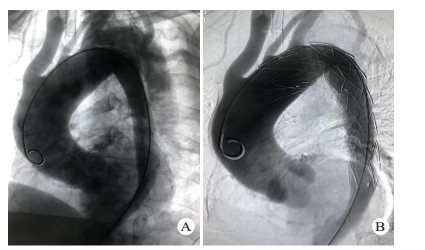

1 资料与方法 1.1 一般资料全组共14例,男性11例,女性3例,年龄23~71岁。急诊入院时间为伤后1~18 h。致伤因素包括车祸伤7例,高处坠落伤5例,重物砸伤1例,胸部击打伤1例; 车祸伤、高处坠落伤等钝性损伤患者不同程度伴有脑部受损,腹腔脏器破裂,血气胸或四肢、骨盆、肋骨、脊椎等骨折。其中伴血胸7例,肋骨骨折5例,四肢骨折3例,肝破裂1例,脾破裂1例,消化道穿孔1例,脑部受损1例,骨盆骨折1例,脊椎骨折1例。既往高血压病史5例。所有患者均由胸腹主动脉断层摄影血管造影(computed tomography angiography,CTA)明确诊断,均为Stanford B型主动脉夹层。夹层累及范围包括:胸主动脉夹层10例,胸腹主动脉夹层4例,肠系膜上动脉、肠系膜下动脉、左肾动脉受累各1例。本研究获得医学伦理委员会批准,编号:2018ER(A)037。治疗及检查均获得患者或家属知情同意。部分患者术前影像学资料见图 1。

| 图 1 患者男性,43岁,因车祸伤致胸背部疼痛入院,CTA诊断为TAD(A:普通胸片提示上纵隔明显增宽,隐约可见主动脉弓,左侧胸腔可见包裹性积液; B:胸部CT示降主动脉分层,可见真假腔,并可见左侧胸腔积液; C:胸腹部CTA提示自降主动脉起始部至前动脉起始部主动脉夹层,主动脉内径增宽; D:术后1年胸腹部CTA,支架位置良好,无移位,无内漏,无新发夹层或动脉瘤) |

术后通过门诊及电话密切随访,随访截止时间2019年8月,随访内容包括患者症状及生活质量,术后3、6、12个月及以后每年复查1次CTA,明确有无内漏、支架移位(图 1D)、截瘫、缺血性脑卒中、左上肢缺血及新发夹层或动脉瘤等并发症。